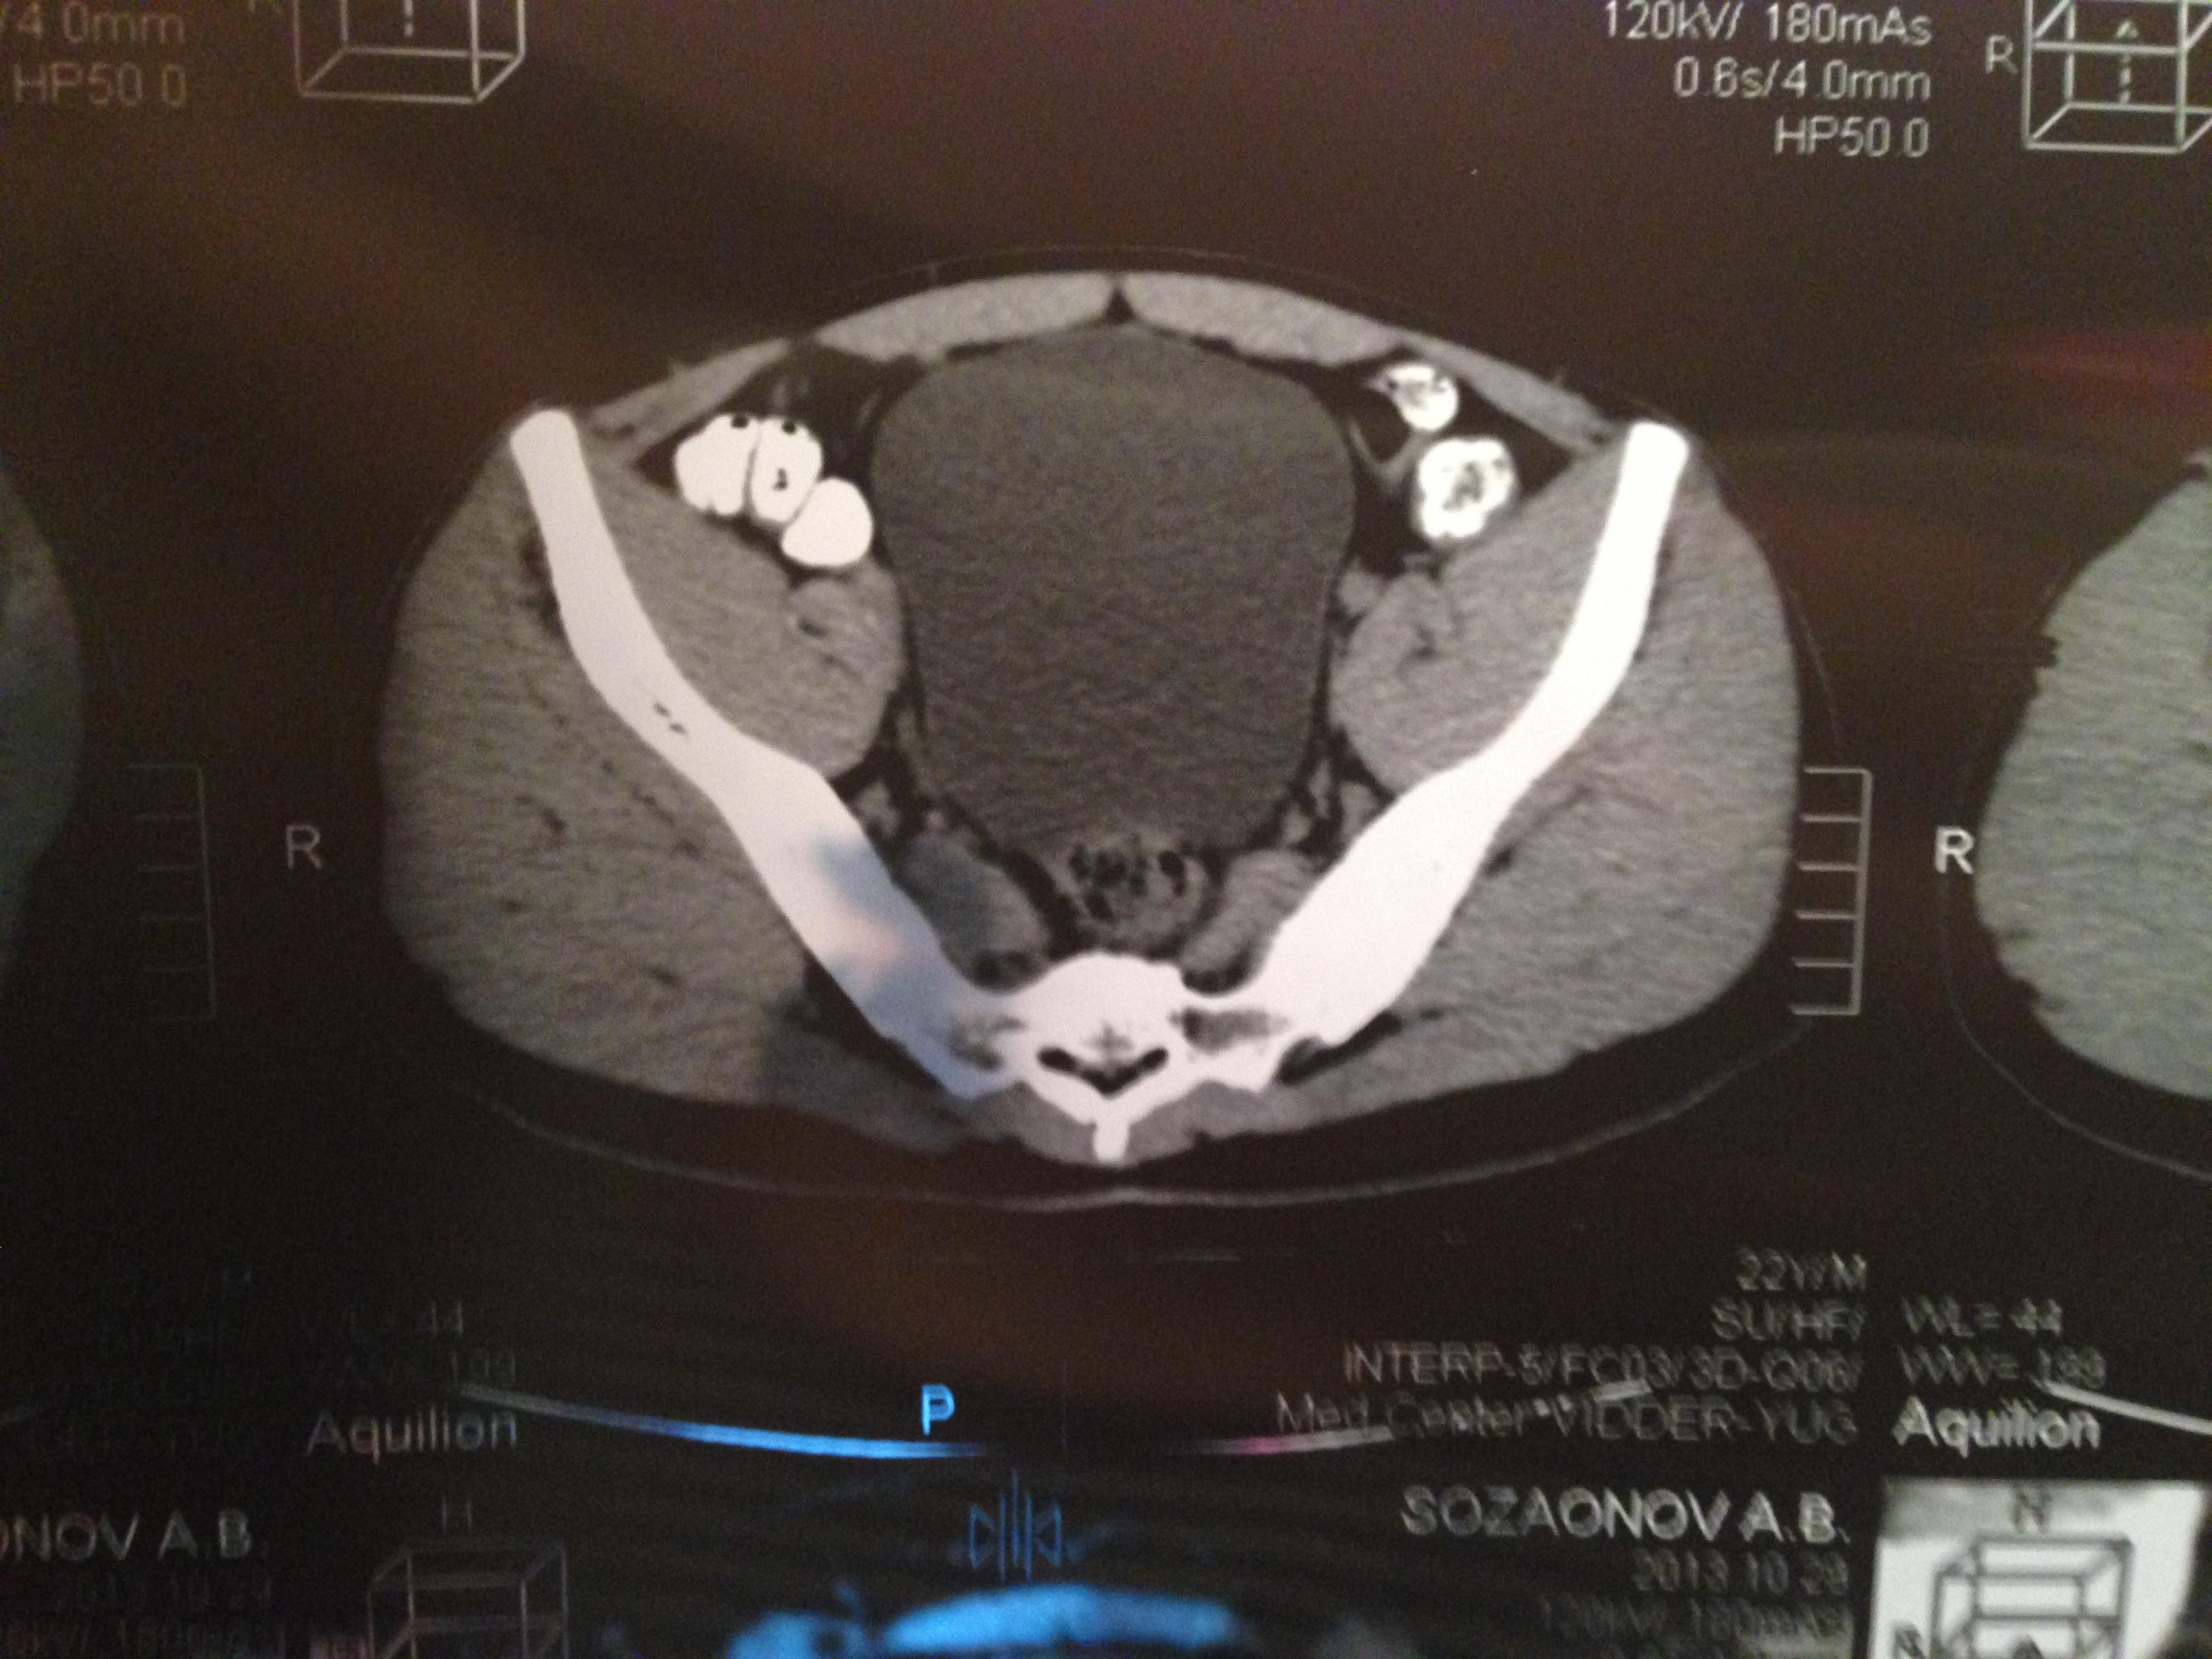

проведена МСКТ области таза!Внеорганных дополнительных патологических образований,лимфаденопатии или свободной жидкости в области таза не выявлено.

Мочевой пузырь-наполнен,стенки не утолщенны,паравезикально-без грубой органки.

Граница между предстательной железой и пузырем несколько четкая,контур пузыря на данном уровне не деформирован.

Предстательная железа-без грубой органики,еденичные микрокальцинаты.

Семенные пузырьки-конфигурация не совсем типична,примерный размер правого 26*28мм.Отмечаются признаки кистовидной трансформации и микрокальцинации обоих пузырьков.Наибольшая из кист слева достигает 9 мм.Обращает на себя внимание неравномерная кальцинация стенок крупных регионарных(текстикулярных)артерий с обоих сторон.

Костно-деструктивных изменений характерных для mts со стороны костей таза не отмечено.

Параректальная клетчатка-не изменена,патологически увеличенных лимфоузлов в параректальном пространстве не отмечено.M.m.levator ani-без особенностей.

Заключение:на момент исследования,КТ-данных за наличие внеорганных дополнительных патологических образований,лимфоденопатии или свободной жидкости в области таза не выявлено.КТ-признаки в пользу проявлений калькулезного везикулита с элементами кистовидной трансформации семенных пузырьков.